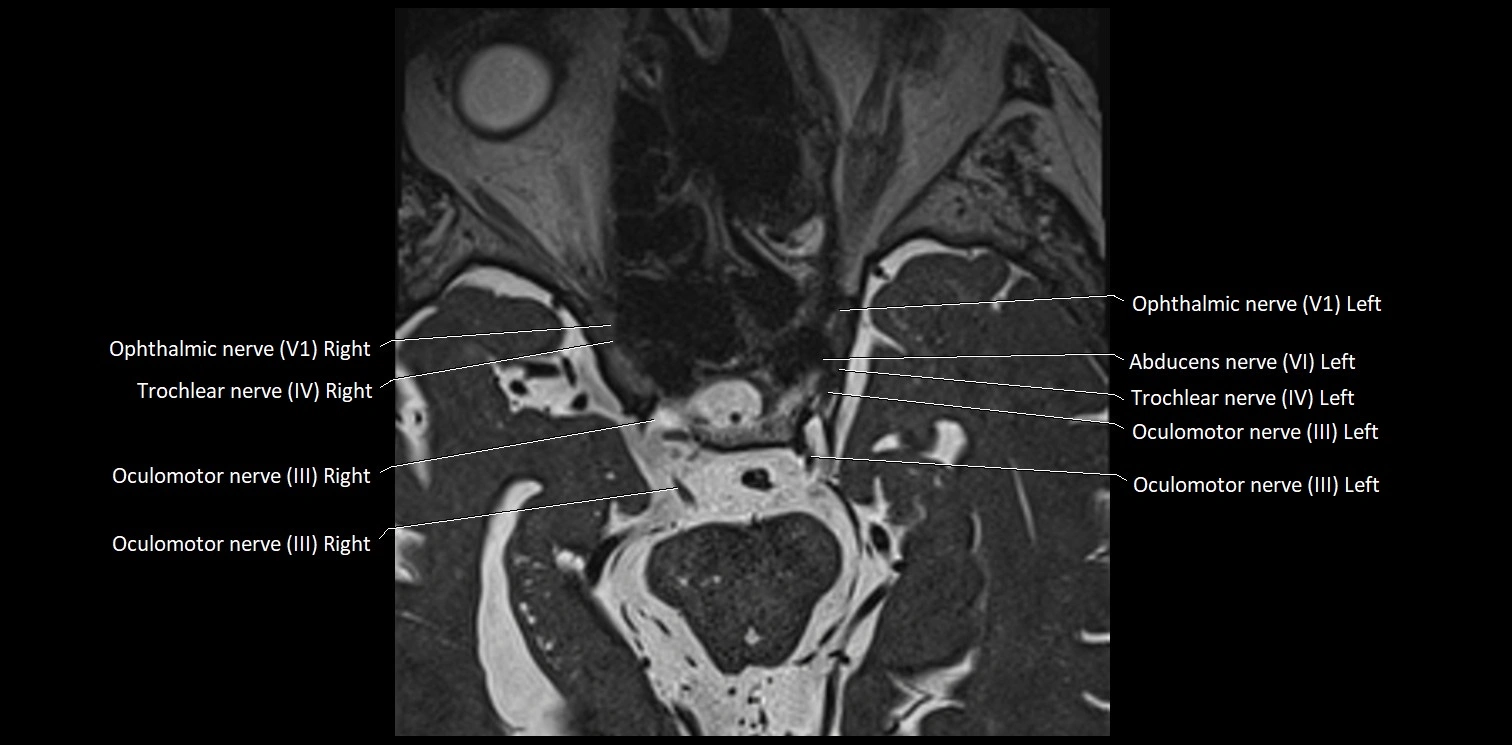

MRI images

image